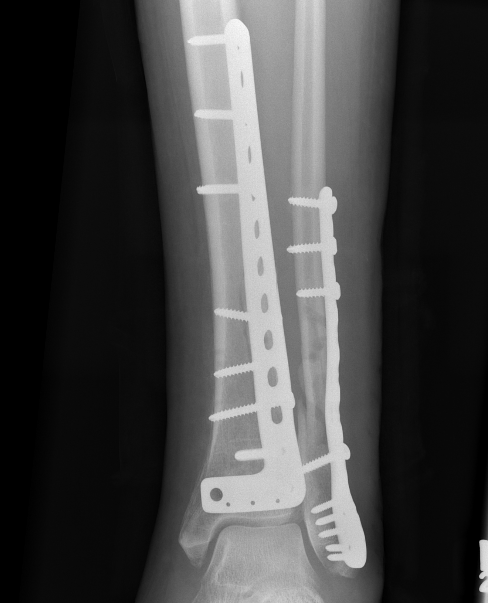

Anterolateral / anterocentral approach

Indication

- anterolateral / Chaput fragment

- valgus configuration

- anterolateral plate

Issue

- will not stabilize medial fragments

- need separate incision